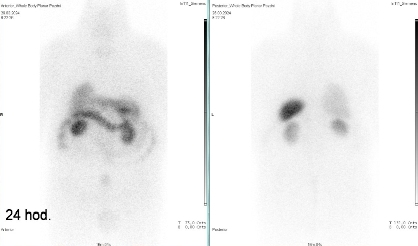

Scintigrafie Octreoscanem:

I. v. jsme aplikovali 190 MBq analogu somatostatinu značeného 111In

(přípravek OctreoScan firmy Curium Netherlands B. V.) a provedli pomocí hybridní tomografické scintilační kamery Symbia Intevo firmy Siemens opatřené kolimátory pro střední energie planární celotělovou scintigrafii a cílenou tomografickou scintigrafii (SPECT) břicha a pánve kombinovanou s CT za 4 a 24 hod.

(obr. 3-7).

/ Obr. č. 3: Celotělová scintigrafie v přední a zadní projekci 4 hod. po aplikaci OctreoScanu.

/ Obr. č. 6: Celotělová scintigrafie v přední a zadní projekci 24 hod. po aplikaci OctreoScanu.

Pozorujeme pouze fyziologickou depozici radioaktivity v játrech, slezině, ledvinách, močovém měchýři a ve střevech.

Závěr: neprokazujeme jednoznačná patologická ložiska svědčící pro přítomnost tkáně se zvýšenou hustotou somatostatinových receptorů.

Závěr:

Patologické ložisko ventrálně od D2 duodena patrné při vyšetření před 13 měsíci (před operací) již není zobrazeno.